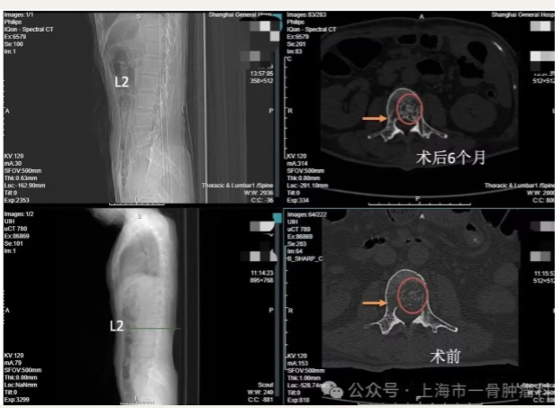

读片:CT及MRI检查提示,T2,L2,L5椎体骨质破坏,红色箭头所指为转移病灶所在位置,可见L2椎体病灶已侵犯后壁,突入椎管内。

术后6月与术前CT对比,红色圆圈处可见术后6月,椎体后壁有明显骨化形成,黄色箭头处可见术后6月,非消融侧病灶亦有明显缩小